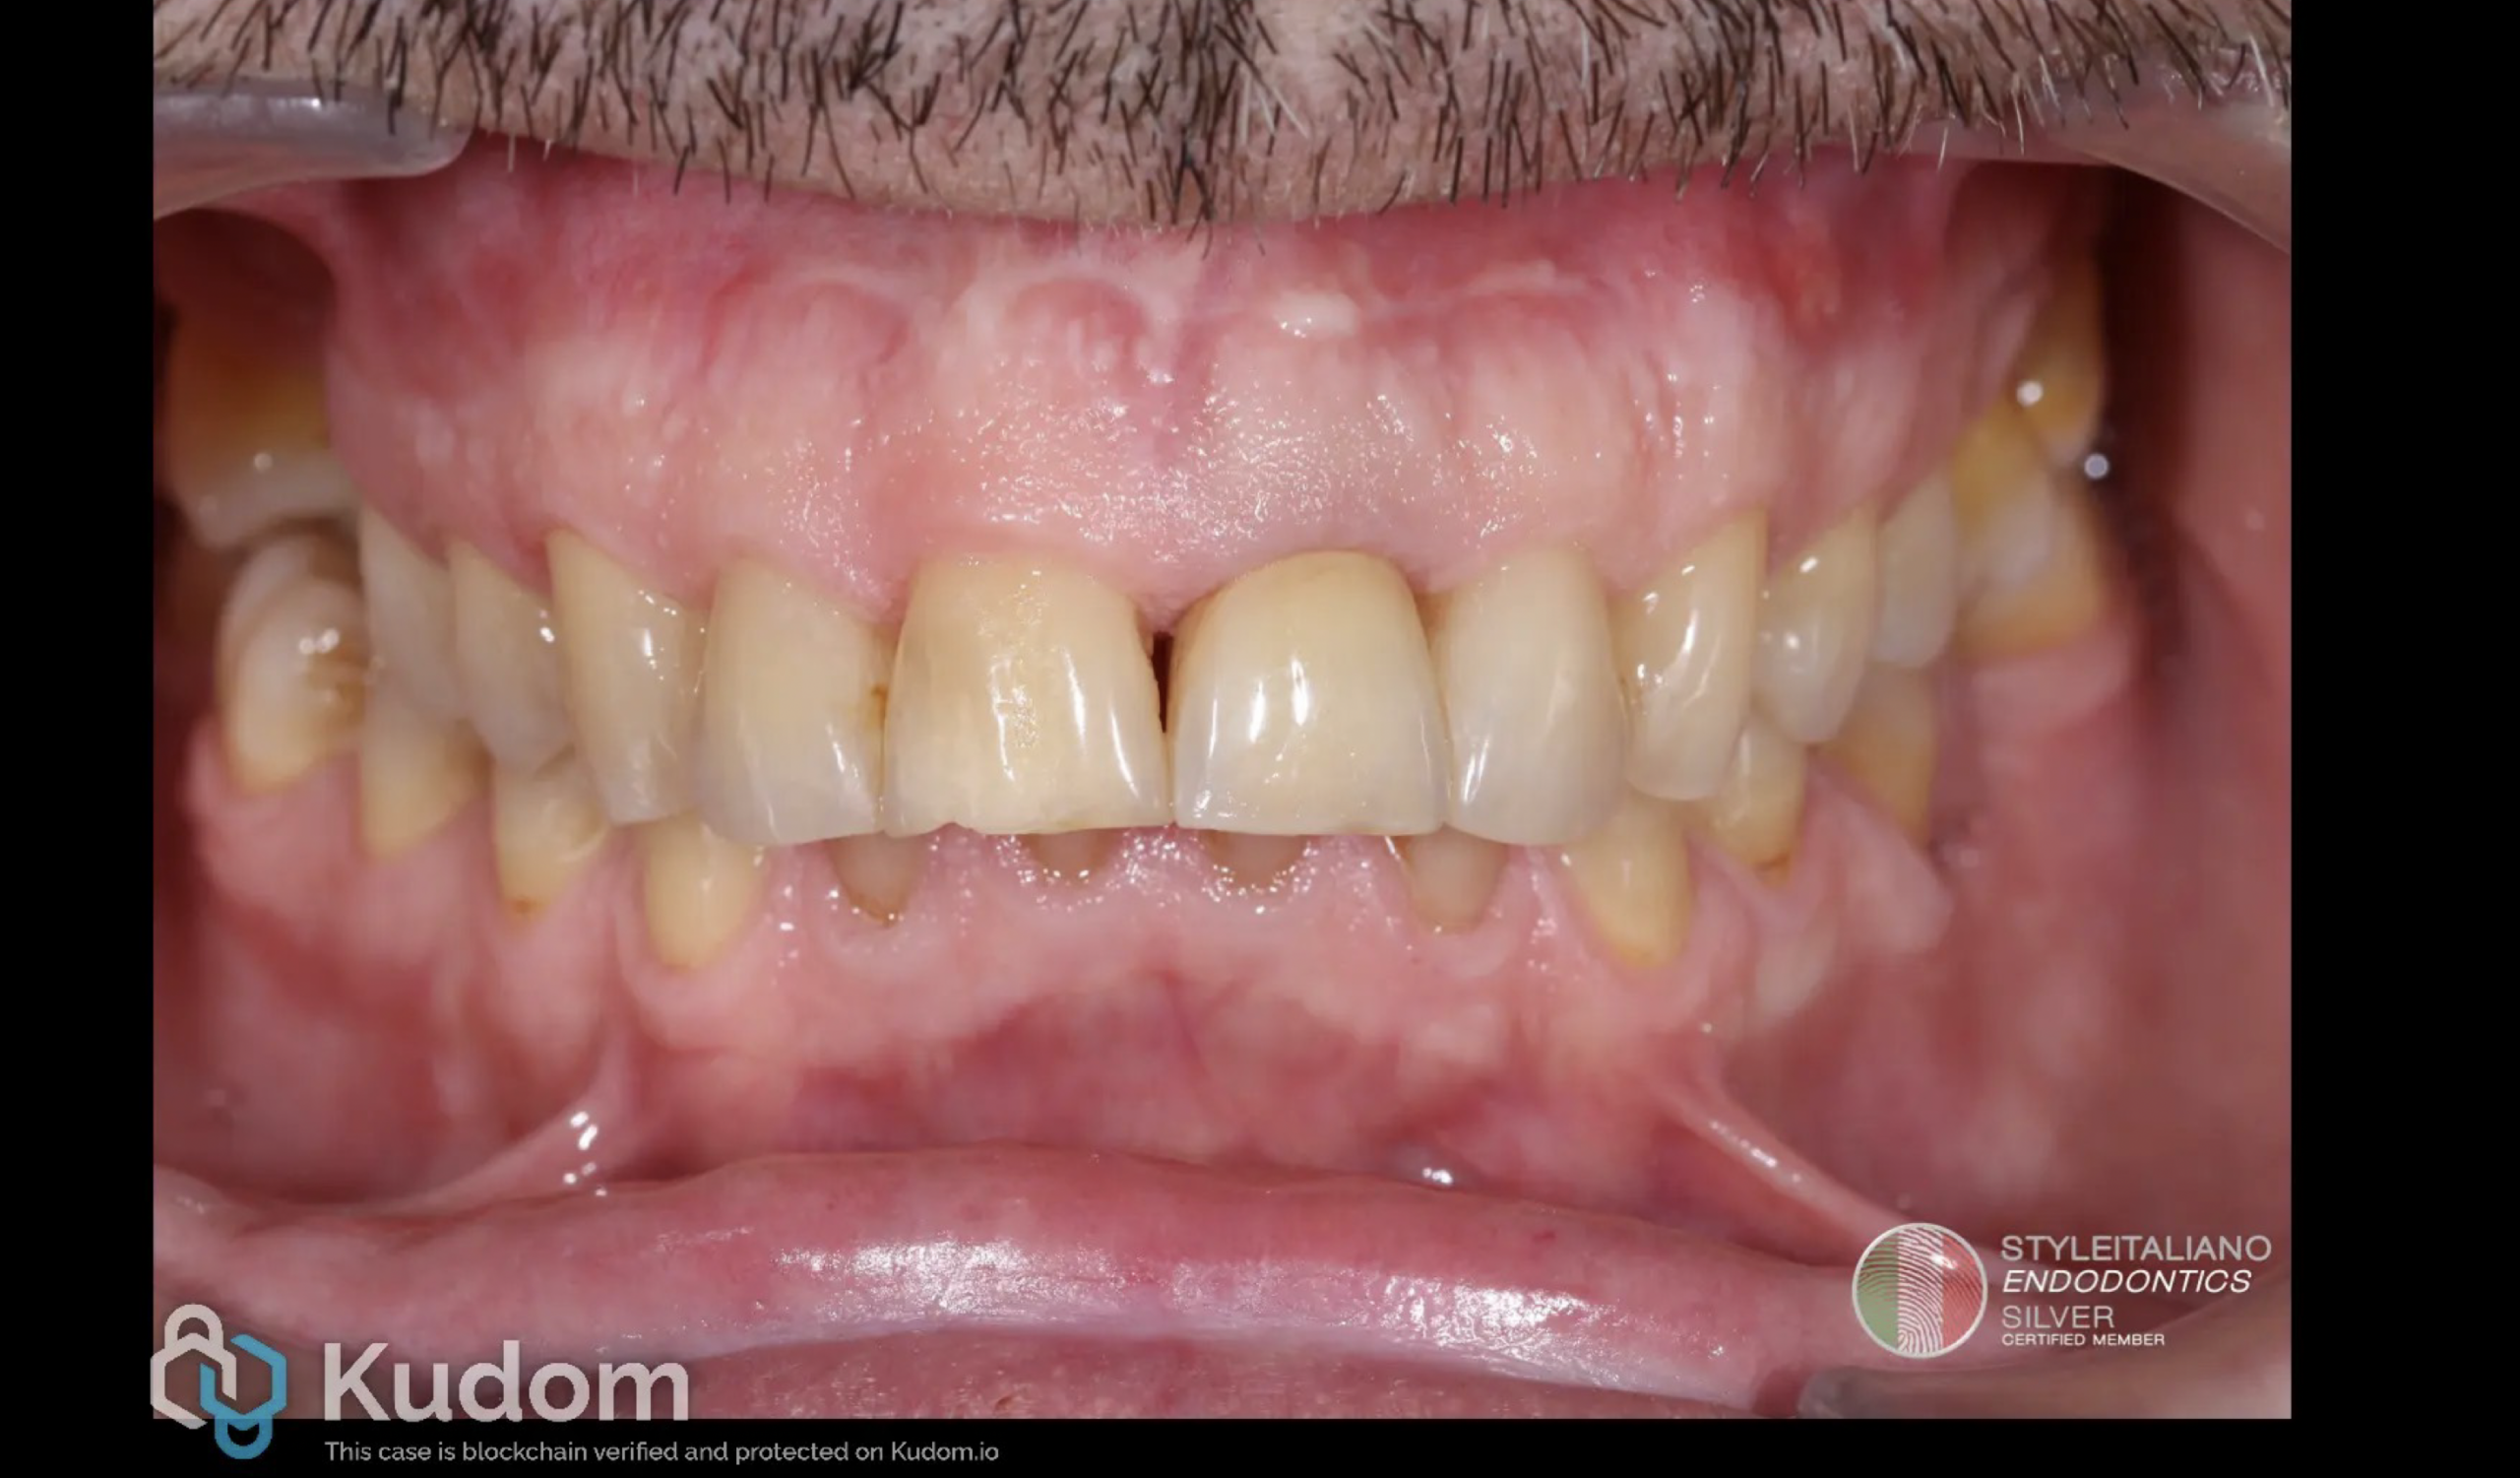

Fig. 2

For the treatment plan, non-surgical endodontic treatment was proposed and accepted by the patient. The treatment was performed under an operating microscope and rubber dam isolation. After removing the crown and establishing access with Ultrasonic tips, the canal was scouted with 10k and 15k stainless-steel hand files. Working length was established with the help of an electronic apex locator and confirmed by CB-CT measurement. The canal was shaped with Reciproc blue files until 40/06 and the apical one third was prepared by hand files until 60/02. NaOCl 5.25% was used throughout the endodontic procedure to facilitate chemical disinfection and removal of debris. After shaping, the hypochlorite was activated with sonic tips and, once cleansing was completed, we proceeded with 17% EDTA irrigation in order to remove the smear layer. After the final irrigation, the canal was dried using paper points and the working lenght was again checked by the paper point technique as a third complementary method to ensure the corect initial measurement of the working lenght [7]. A collagen sponge was placed as a resorbable internal matrix (apical barrier) beyond the apical foramen to prevent extrusion of filling materials [8] as seen in Figure 2. This colagen sponge acts as a stable base for compacting the filling material, allowing for a single-session, safe, and efficient root canal treatment of open apices [8].